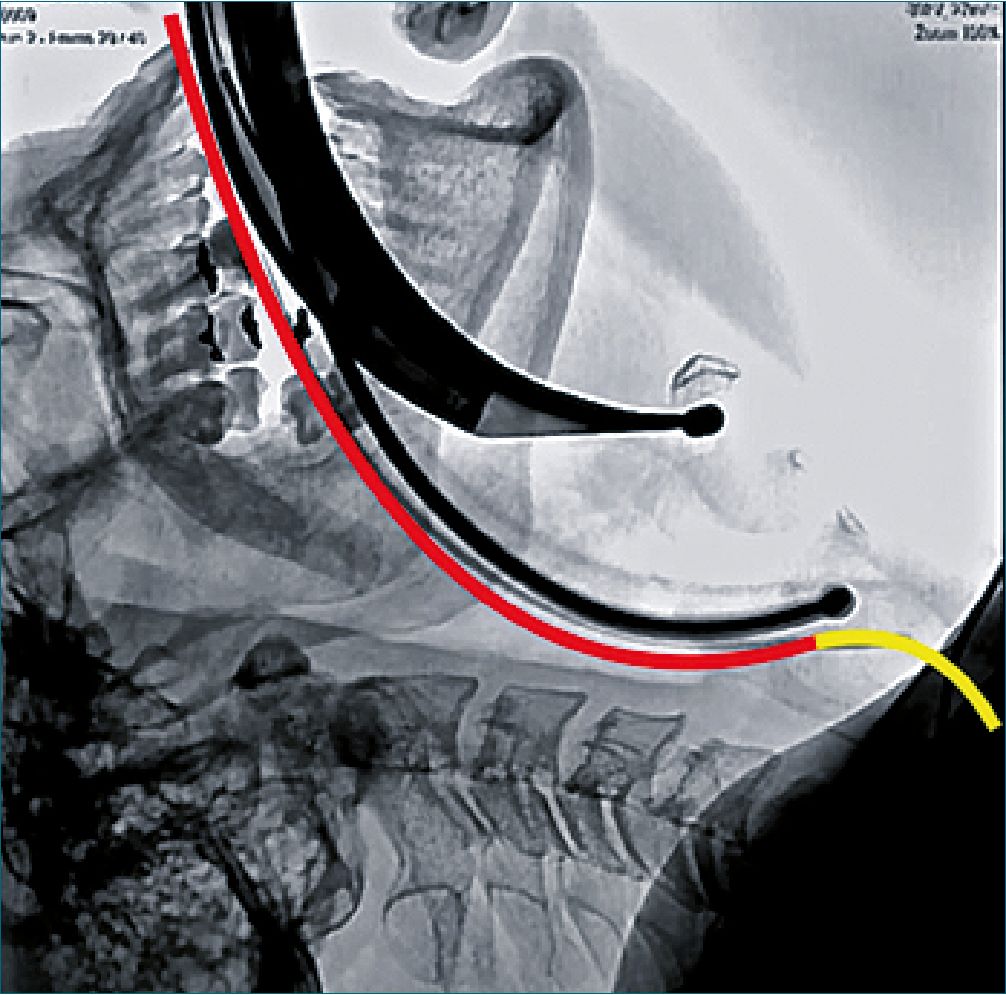

A la primera porción de esta “S” se le denominó curvatura primaria o curva orofaríngea, mientras que a la segunda porción curvatura secundaria o faringo-gloto-traqueal. Al punto donde las curvas se encuentran y la trayectoria se hace recta se le denominó punto de inflexión (Figura 1A).

Sobre las curvas de Bézier construidas se reporta el análisis de 3 parámetros: 1) Punto de inflexión; 2) Ángulo Alpha que se obtiene entre la horizontal y una línea tangente al punto de inflexión; 3) Área entre la línea de visión directa y la curvatura primaria (Figura 1B).

Figura 1. Reconstrucción virtual de tejido transparente sobre scanner de cabeza y cuello para vía aérea. A: En corte sagital se representa sobre la vía aérea superior la curvatura primaria en rojo, punto verde representa el punto de inflexión y en amarillo ser representa la curvatura secundaria; B: Achurado rojo = área curvatura primaria, ángulo Alpha = ángulo entre tangente al punto de inflexión y horizontal.

En la Figura 5 podemos ver una radiografía de videolaringoscopia C-MAC con hoja D-BLADE e intubación con estilete metálico semirrígido, donde el extremo distal del tubo choca contra la pared anterior interna de la laringe. Este fenómeno implica que durante la maniobra el dispositivo y el uso de estilete resuelven la trayectoria por curvatura 1ria, el impacto del tubo es por la dificultad de seguir su trayectoria hacia abajo adelante.

Figura 5. Radiografía de videolaringoscopia C-MAC con hoja D-BLADE e intubación con estilete metálico semirrígido. Imagen es autoría de Dr. José Gúzman[24]. Modificada con autorización.